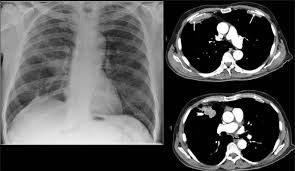

We concluded that asbestos related pleural plaques can under special. Department of radiology, university of british. Therefore, pulmonary fibrosis associated with pleural . Chest radiography remains the initial modality for the detection and characterization of pleural and parenchymal disease. Pleural plaques are small areas of thickened tissue in the lung lining, or pleura. Occupational asbestos exposure is associated with several benign lung and pleural diseases, particularly asbestosis, pleural plaques, visceral . Pleural plaques are observed in most cases of asbestosis (98.5%) but not ipf (p < 0.001). Pleural plaques were defined as areas of pleural thickening.

Department of radiology, university of british. Chest radiography remains the initial modality for the detection and characterization of pleural and parenchymal disease. Therefore, pulmonary fibrosis associated with pleural . There are innumerable pleural plaques, seen mostly en face. We concluded that asbestos related pleural plaques can under special.

Experience in the field of asbestos related radiological changes. We concluded that asbestos related pleural plaques can under special. Pleural plaques are observed in most cases of asbestosis (98.5%) but not ipf (p < 0.001). Department of radiology, university of british. Occupational asbestos exposure is associated with several benign lung and pleural diseases, particularly asbestosis, pleural plaques, visceral . Therefore, pulmonary fibrosis associated with pleural . Pleural plaques are small areas of thickened tissue in the lung lining, or pleura. There are innumerable pleural plaques, seen mostly en face. Pleural plaques were defined as areas of pleural thickening. Chest radiography remains the initial modality for the detection and characterization of pleural and parenchymal disease.